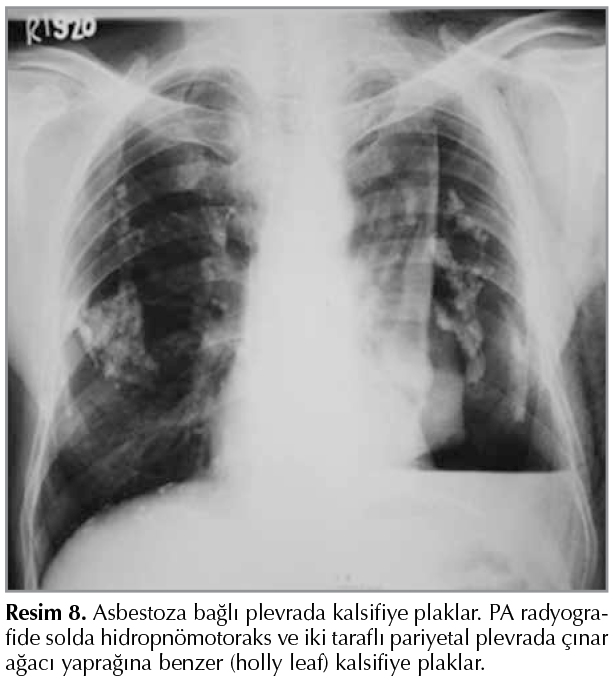

Hidatik Kist Hastalığı

Hidatik kist nadiren plevral boşlukta ve interlober fiss?rde lokalize olmaktadır (primer plevral hidatidozis). Evcil k?peklerin neden olduğu hidatik kistle infekte olgularda sık g?r?lmemektedir (36). Plevral boşlukta ve interlober fiss?rdeki intakt hidatik kist PA radyografide homojen yoğunluk artışı g?stermektedir (Resim 11). USG'de ekoik kaps?ll? sıvı i?eren anekoik kistik lezyon şeklinde g?r?lmektedir. BT'?de diğer organlarda g?r?len bulgulara benzer şekilde kaps?ll? sıvı i?eren d?ş?k dansiteli kistik lezyon şeklinde g?r?lmektedir. MR g?r?nt?leme yumuşak doku kontrast ?zelliğine bağlı olarak gerek plevral boşluktaki, gerekse interlober fiss?rdeki kistik lezyonu diğer y?ntemlere g?re daha ayrıntılı g?stermektedir (37,38). Plevral boşluktaki intakt hidatik kist spontan olarak veya travma nedeniyle perfore olabilir Germinatif membranın perikistten ayrılması ile perfore hidatik kist i?in olduk?a spesifik bulgu olan g?r?n?m meydana gelmektedir. Bu olgularda PA radyografide plevral ef?zyona benzer bulgu ve hava-sıvı seviyesi g?r?lebilir. Bu olgularda yumuşak doku kontrast ?zelliği ve ?? boyutlu g?r?nt?leme ?zelliği nedeniyle MRG daha ayrıntılı bilgi vermektedir (Resim 12) (37,38).

Resim 11

Resim 12